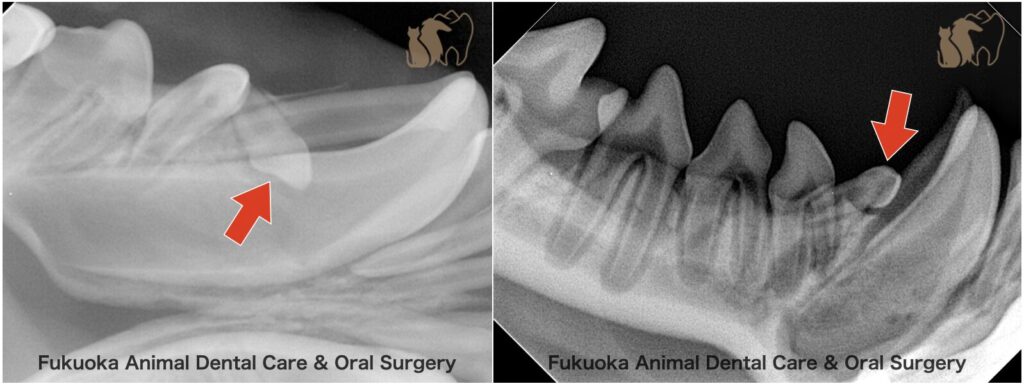

下顎第一前臼歯を原因とする含歯性嚢胞

症例:2歳6ヶ月齢、チワワ

主訴:下顎歯肉の腫れ

検査:歯科レントゲン検査で左下顎第一前臼歯の埋伏を認めた。歯肉の腫れは波動感を伴っていました。

治療:埋伏歯の抜歯および嚢胞壁を可能な限り除去を実施しました。

病理検査:摘出した嚢胞壁の病理検査結果により、歯原性嚢胞と診断されました。

確定診断:臨床所見および病理検査結果より、下顎第一前臼歯を原因とする含歯性嚢胞と確定診断しました。

コメント:明らかな痛みなどの症状は認められませんでしたが、飼い主様が歯肉の腫脹に早期に気づかれたことが診断につながりました。含歯性嚢胞により下顎骨は菲薄化しており、病的骨折のリスクがある状態です。そのため、日常生活においては顎に強い力が加わらないよう注意が必要です。